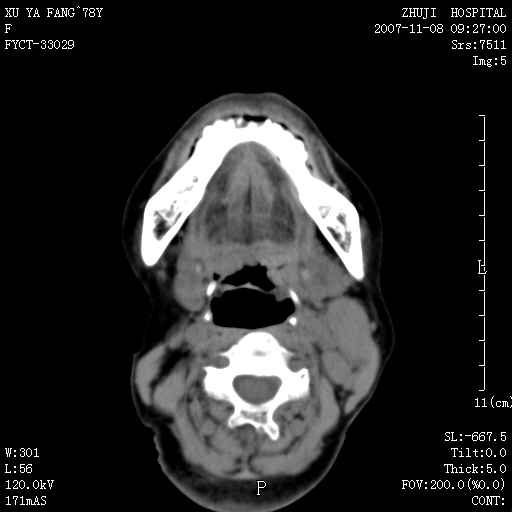

女性,78y,发现左侧扁桃体区肿大,表面糜烂.及颈部肿块一周.

左侧扁桃体恶性肿瘤伴淋巴结的转移

主要的鉴别是扁桃体的炎性增生与脓肿,假如没有淋巴结的肿大鉴别还是有困难的,增强脓肿是环形强化,临床症状也可鉴别

左侧扁桃体恶性肿瘤伴淋巴结的转移;考虑为扁桃体癌可能。此部位的恶性肿瘤以扁桃体癌和淋巴瘤多见,相对来说淋巴瘤范围较广泛些。有时两者区别较难,需要活检。

左侧扁桃体区软组织占位,强化后边界清晰,密度均匀,周围脂肪间隙清晰。周围淋巴结肿大。首先考虑扁桃体炎性增生,不排除扁桃体区的恶性肿瘤!!不知临床上有无发烧??/wbc是否增高??

左侧口咽侧壁巨大软组织肿块突入口腔,增强密度均匀,中度增强,左颈部多发肿大淋巴结,考虑左侧扁桃体恶性肿瘤(淋巴瘤还是癌不好鉴别)并淋巴结转移。 期待病理!